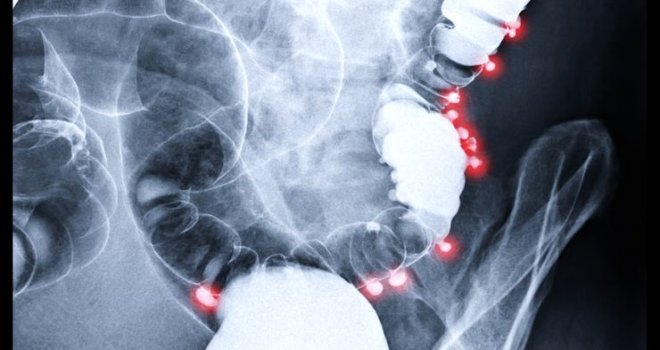

Son 15 yıldır ölümler anal kanser yüzünden gerçekleşiyor

Anal kanseri, tüm kanser teşhislerinin sadece yüzde ikisini oluşturan, nispeten nadir görülen bir hastalık şeklidir. Neredeyse tüm anal kanseri vakalarına cinsel açıdan aktif kişilerin yüzde 80’ini etkileyen papilloma virüsü (HPV) neden olur ve kendi içinde 100 farklı tipi vardır.

Ulusal Kanser Enstitüsü Dergisi'nde yayınlanan yeni araştırmanın bulguları da özellikle anal kanser oranlarında dik bir artış izlendiği yönünde.2001 ve 2016 yılları arasında toplam 68.809 kişiye anal kanser teşhisi kondu ve bunlardan 12.111’i bu hastalıktan öldü.Teşhisler ve ölümler her yıl yaklaşık yüzde üç arttı; elimizdeki bu yeni araştırmalara göre anal kanseri, günümüzde en hızlı yayılan kanser türlerinden biri. Anal kanserine erken teşhis konulduğunda sonuçlar çok daha iyi olur ve hastanın hayatta kalma oranı yaklaşık yüzde 80'e kadar artar.

Hastalık lenf bezlerine yayıldığında ise bu oran yüzde 60'a düşer.

Anal kanserinin belirtileri aslında oldukça belirgindir; anal bölgede ağrı, basınç veya topaklar, sıra dışı akıntı, kanama veya bağırsak hareketlerinde değişiklikler gibi diğer daha genel koşullarla kolayca karıştırılabilirler.